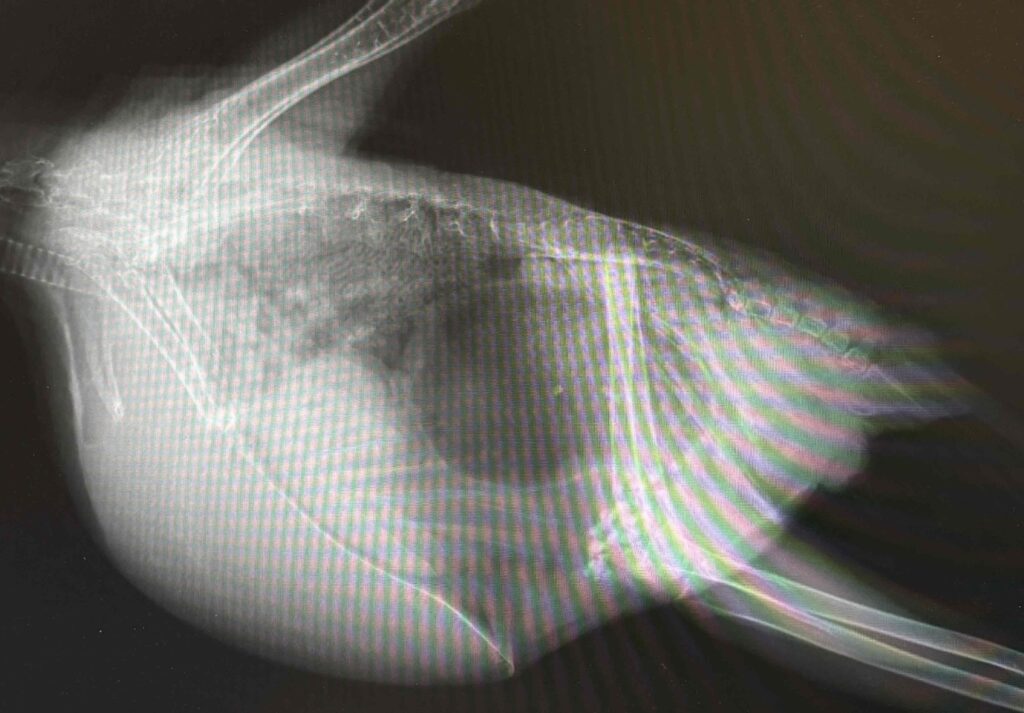

腺胃拡張症 投稿日 2024年8月14日 著者 s.takagi カテゴリー 消化器疾患 腺胃拡張はレントゲン検査にて判定することができます。まだ何も症状がないこともあれば、吐き気などの症状が出ている場合もあります。腺胃が拡張してしまう原因は胃腸機能低下、神経症状による随伴、多飲による腺胃内への水の蓄積などがありますが、ボルナウイルス感染の可能性も考える必要があります。